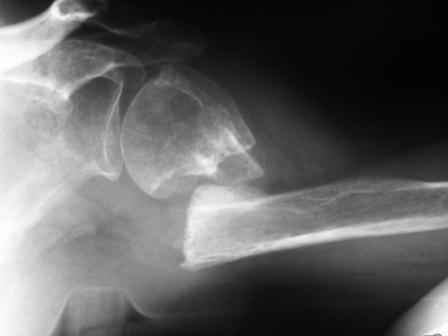

ложный сустав плеча

Уважаемые коллеги! Госпитализирована больная 51года. Травма - перелом хирургической шейки плеча в феврале 2009г.

Лечилась по месту жительства Лонгетной гипсовой повязкой. На фоне сформировавшегося ложного сустава работает маляром. Объем движений и сила естественно ограничены. При обсуждении тактики лечения возникли разногласия по поводу вида остеосинтеза и его целесообразности.